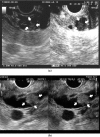

Accumulated evidence has revealed that endoscopic ultrasonography (EUS) has had a great impact on the clinical evaluation of pancreatic cancers. EUS can provide high-resolution images of the pancreas with a quality regarded as far surpassing that achieved on transabdominal ultrasound (US), computed tomography (CT), or magnetic resonance imaging (MRI). EUS is particularly useful for the detection of small pancreatic lesions, while EUS and its related techniques such as contrast-enhanced EUS (CE-EUS), EUS elastography, and EUS-guided fine needle aspiration (EUS-FNA) are also useful in the differential diagnosis of solid or cystic pancreatic lesions and the staging (T-staging, N-staging, and M-staging) of pancreatic cancers. In the diagnosis of pancreatic lesions, CE-EUS and EUS elastography play a complementary role to conventional EUS. When sampling is performed using EUS-FNA, CE-EUS and EUS elastography provide information on the target lesions. Thus, conventional EUS, CE-EUS, EUS elastography, and EUS-FNA are essential in the clinical investigation of pancreatic cancer.